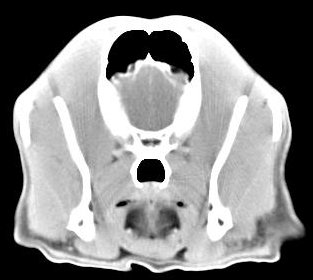

imágenes de TC en el perro | ||||||||||

ejemplo de imágenes de TC en el perro. Nótese la celulitis en la región parotídea izquierda | ||||||||||